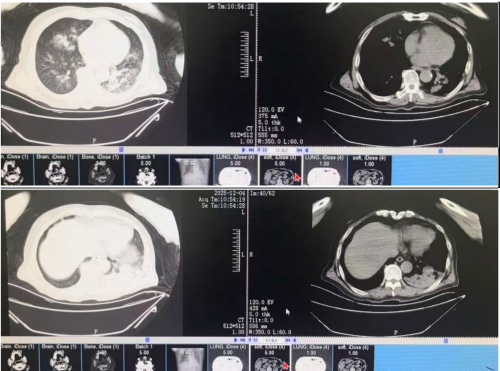

2025-12-04 胸部CT:

12月6日肺泡灌洗液NGS结果提示肺炎链球菌 37333*10^9/L, 肺炎克雷伯杆菌 554*10^3/L,甲型流感病毒H3N2 10783*10^6/L